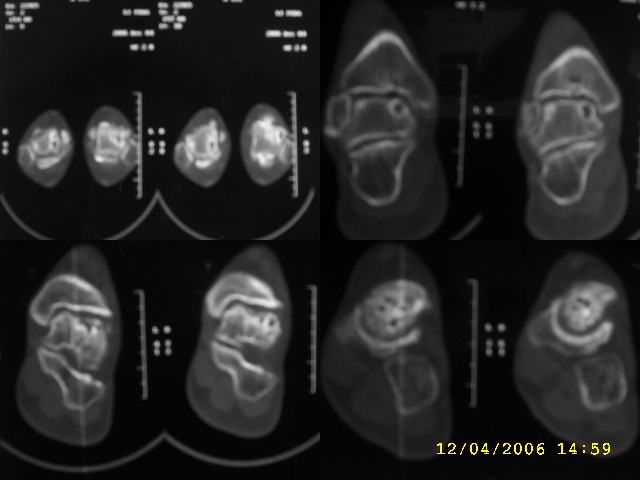

男,44,双踝关节肿胀,疼痛,活动受限2月余。无外伤史。

双侧距骨及胫骨都有骨质破坏,还很对称,最好追问一下病史,看这人有没有痛风。

双侧距骨可见多发囊变区,边缘硬化内可见更高密度影,考虑1双侧踝关节结核2退行性骨关节病

双侧距骨关节面下可见多发囊变区,边缘硬化内可见更高密度影。考虑:双踝剥脱性骨软骨炎。

双侧距骨及胫骨都有骨质破坏,边缘硬化内可见更高密度影,双侧对称性发病,踝关节及跟距关节内低密度影(气体影?),双侧对称发病基本可以排除关节结核及化脓性关节炎,痛风性关节炎以第1跖趾关节为典型发病部位,临床症状间歇性发作,受累关节非对称性肿胀与本例不符,首先考虑退行性骨关节病,请结合抗\"o\"及类风湿因子检查排除风湿性关节炎。

跟进!关节间隙明显变窄,诸相对骨性关节面增生、硬化,内见多发囊变,考虑增生性骨关节病!

双侧距骨及胫骨近关节面都有骨质破坏,边缘硬化,唇样变,内可见囊状低密度影,双侧对称性发病,首先考虑退行性骨关节病。